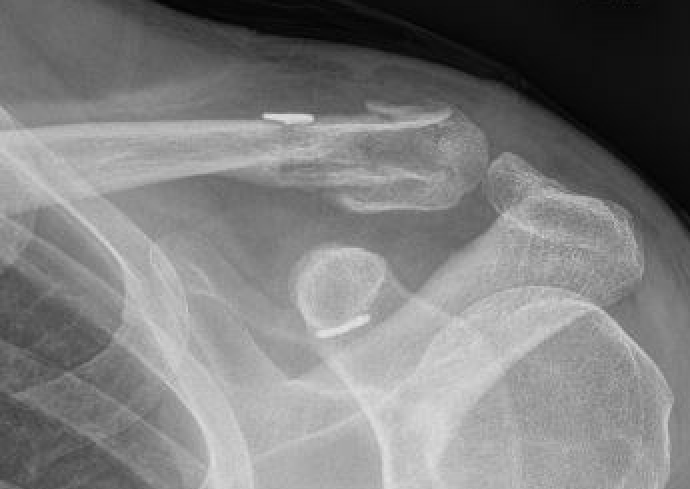

Neer Classification

Fracture lateral to the CC ligaments Non displaced

|

Fracture medial to the CC ligaments CCL ligaments attached to lateral fragment Medial fragment displaced superiorly |

Between conoid and trapezoid Conoid disrupted Trapezoid remains attached to the lateral fragment |

Lateral to CC ligaments Intra-articular extension Stable |

Periosteal sleeve disruption Pediatric Medial fragment displaced |

Comminuted Type II Medial fragment displaced |

Type V